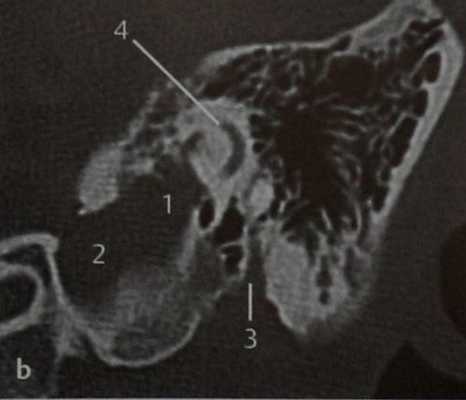

КТ в вертикальной проекции. Наиболее крупная часть опухоли (1) локализуется в крыше луковицы ВЯВ (2) и частично инфильтрирует медиальные сосцевидные ячейки вплоть до средней черепной ямки. Видны шилососцевидное отверстие (3) и задний полукружный канал (4). Как и в данном случае, опухоль эндолимфатического мешка чаще образуется при болезни Гиппеля-Линдау, а вообще эта опухоль встречается редко.